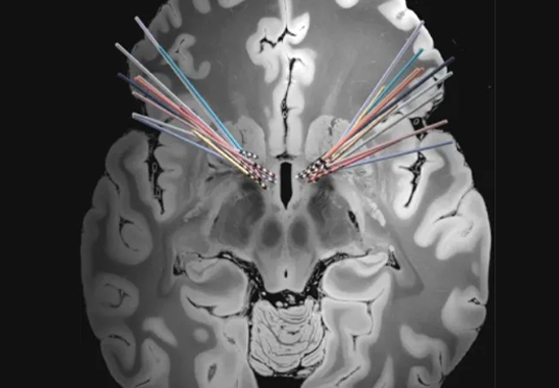

上海市精神卫生中心植入式神经刺激系统用于治疗难治性强迫症的疗效及影响因素研究项目首例受试者开机成功!

上海市精神卫生中心植入式神经刺激系统用于治疗难治性强迫症的疗效及影响因素研究项目第二例受试者开机成功!